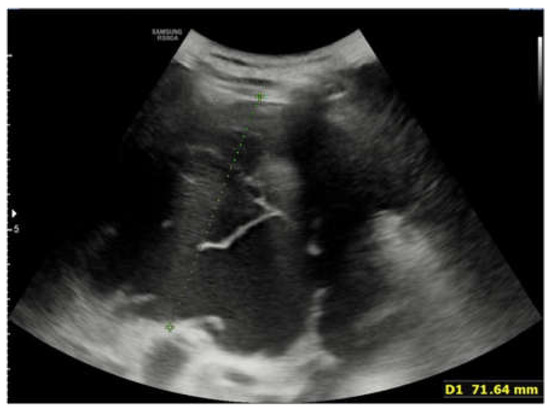

The Key Role of Lung Ultrasound in the Diagnosis of a Mature Cystic Teratoma in a Child with Suspected Difficult to Treat Pneumonia: A Case Report

2. Case Report